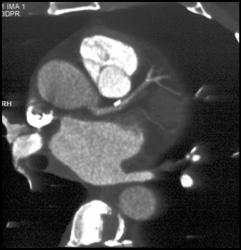

Patent Bypass Grafts